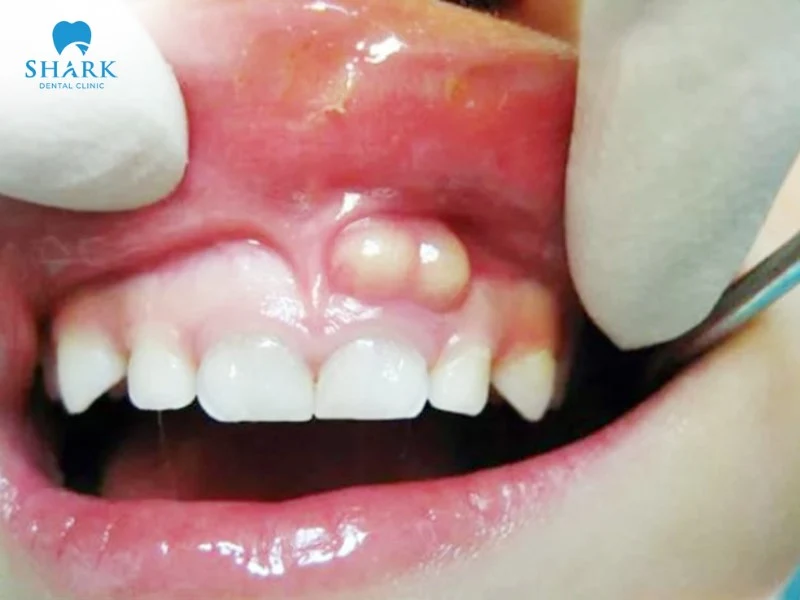

- Xuất hiện lỗ rò (dò nướu): Thường thấy một lỗ rò mủ ở vùng lợi, chảy mủ trắng đục, có mùi hôi, hơi thở có mùi tanh, đôi khi cảm giác sưng và đau giảm dần sau khi mủ chảy ra.